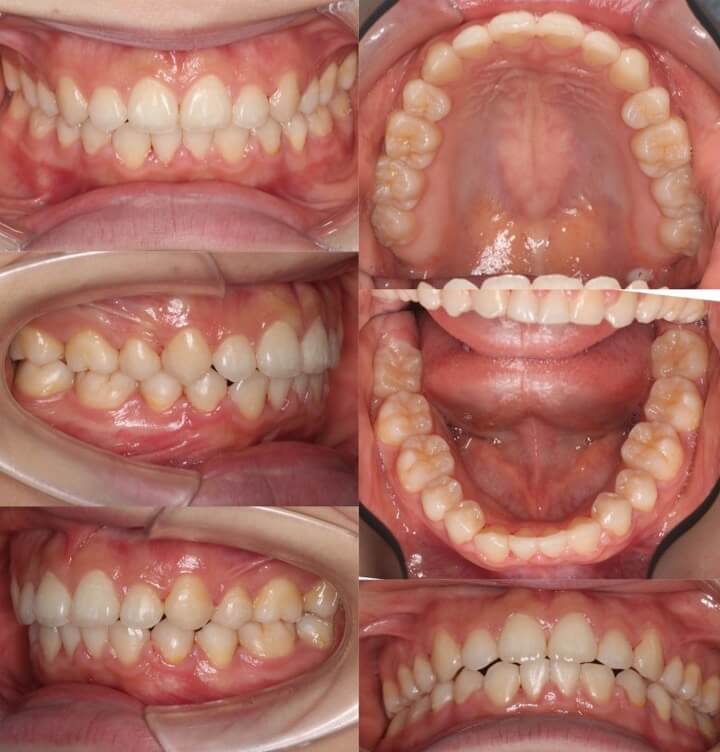

40代女性・先天性欠損2歯・下5欠損

横顔の突出だけではなく、歯茎が少し見えることも気にされていました。下顎ができるくらいまでしっかりと前歯を後方移動させたいという希望からアンカースクリューを使用し前歯を後退させました。先天性欠如の下5番のスペースは乳臼歯があったこともあり、抜歯後は大きく空隙が開きましたが、しっかりと空隙閉鎖を行いました。

<症例概要>

主訴:横顔の突出・ガミースマイル

年齢・性別:40代女性

症状:左右下5番欠損・開咬・下顎後退

治療方針:抜歯空隙閉鎖・下顎臼歯近心移動・

抜歯:上左右4番・下左右乳臼(計2本)

固定装置:歯科矯正用アンカースクリュー

治療装置:唇側矯正装置

治療期間:2年4か月

リテーナー:上下プレートタイプ

治療費用:990,000(税込)

代表的副作用:痛み・治療後の後戻り・歯根吸収・歯髄壊死・歯肉退縮